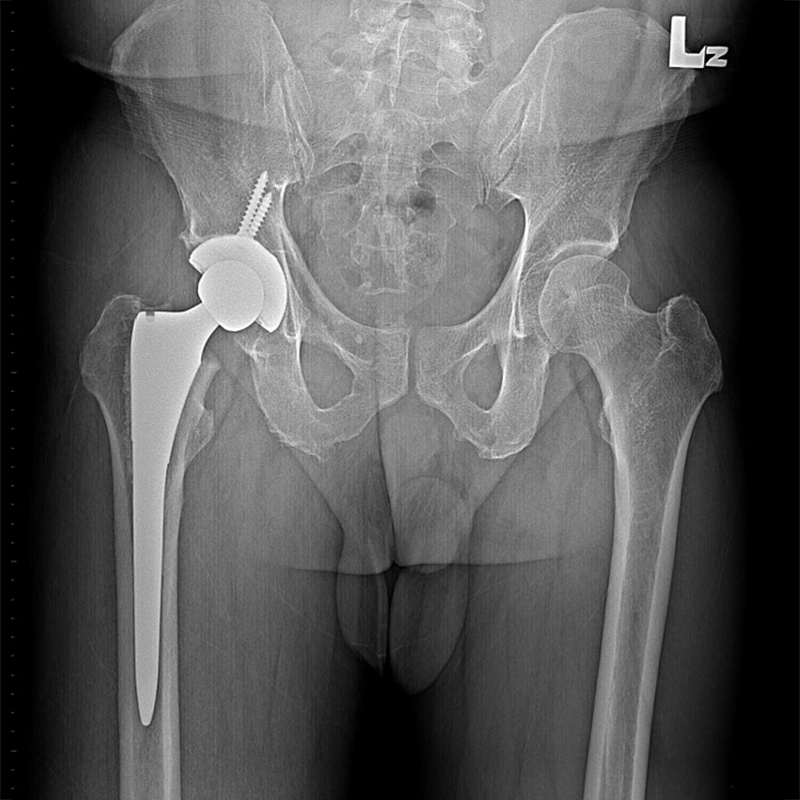

傳統髖關節置換 首頁 案例分享 髖關節手術 傳統髖關節置換 54歲蔡先生退化性關節炎 術前 術後 張女士 51歲 退化性關節炎(DDH先天發育不全 CROWE TYPE 2) 術前 術後 38歲林先生 退化性關節炎 術前 術後 72歲謝女士 退化性關節炎 術前 術後 71歲 謬女士 骨股頭壞死 術前 術後 50歲 郭先生骨股頭壞死 術前 術後 80歲 盧先生骨股頭壞死 術前 術後 林先生 37歲 術前 術後 邱女士 51歲 術前 術後 張女士 50歲 術前 術後